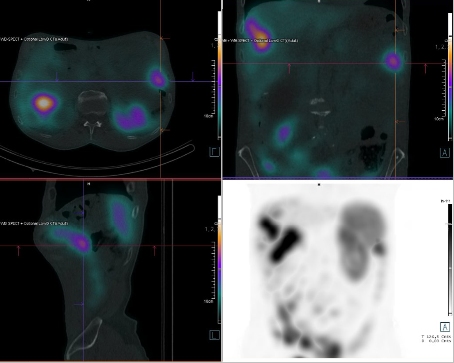

Scintigrafie Octreoscanem:

I. v. jsme aplikovali 190 MBq analogu somatostatinu značeného 111In

(přípravek OctreoScan firmy Curium Netherlands B. V.) a provedli pomocí hybridní tomografické scintilační kamery Symbia Pro.specta X7 firmy Siemens opatřené kolimátory pro střední energie planární celotělovou scintigrafii a cílenou tomografickou scintigrafii (SPECT) břicha a pánve s ldCT za 4 a 24 hod.

/ Obr. č. 1: Celotělová scintigrafie 4 hod. po aplikaci OctreoScanu.

Pozorujeme patologicky zvýšenou depozici radiofarmaka: nejméně čtyři ložiska v pravém jaterním laloku (ložisko s vysokou akumulací laterálně, největší ložisko vysoce akumulující oválného tvaru dorzokaudálně, další dvě malá dorzolaterálně a kraniálně), vícečetná drobná ložiska v břiše a pánvi, zřejmě v uzlinách mezenteria a na peritoneu, ložisko pod dolním okrajem sleziny.

Akumulace dále ve slezině, ledvinách a střevních kličkách představuje fyziologickou distribuci. Vedl. nález obrovská hydronefróza pravé ledviny bez akumulace.

Mnohočetná ložiska patol. depozice Octreotidu odpovídají generalizaci procesu v dutině břišní - játra, mezenterium, karcinomatoza peritonea, pod slezinou.